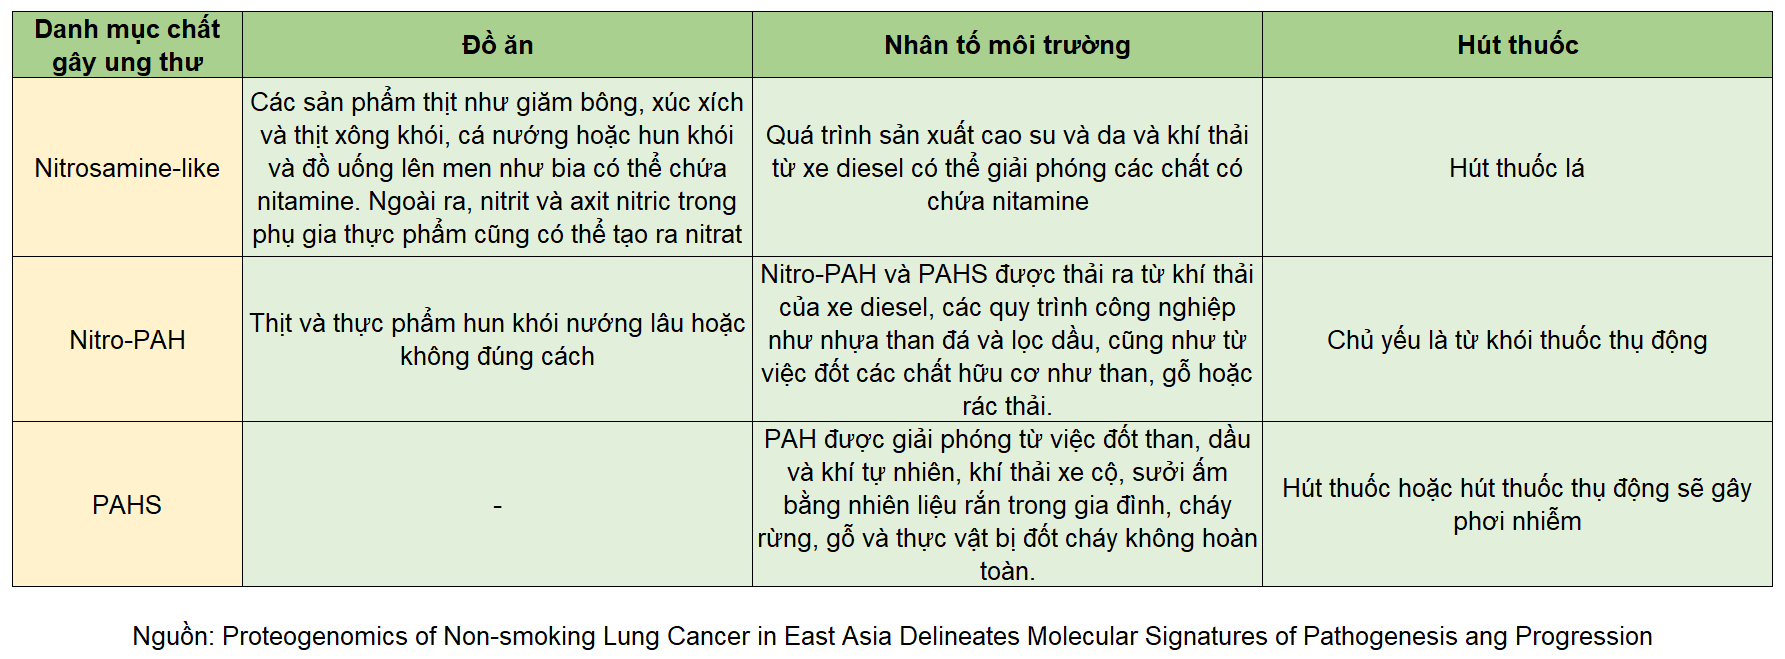

Nguy cơ tiềm ẩn trong thực phẩm và không khí - Phát hiện ra nhiều tác nhân khác gây ra ung thư phổi

- Chúng ta luôn tin tưởng rằng khói thuốc thụ động và khói từ dầu nấu ăn nhà bếp là thủ phạm chính gây ung thư phổi. Tuy nhiên, nghiên cứu mới nhất của Viện Nghiên cứu Khoa học Trung ương đã chỉ ra rằng yếu tố di truyền, phụ gia thực phẩm, chất bảo quản và ô nhiễm không khí cũng là những nguy cơ tiềm ẩn rất đáng quan ngại.

- Vị trí của các gen gây ung thư hoặc chất ức chế khối u chính (vòng ngoài) và sơ đồ mối quan hệ của năm chất gây ung thư (vòng trong).